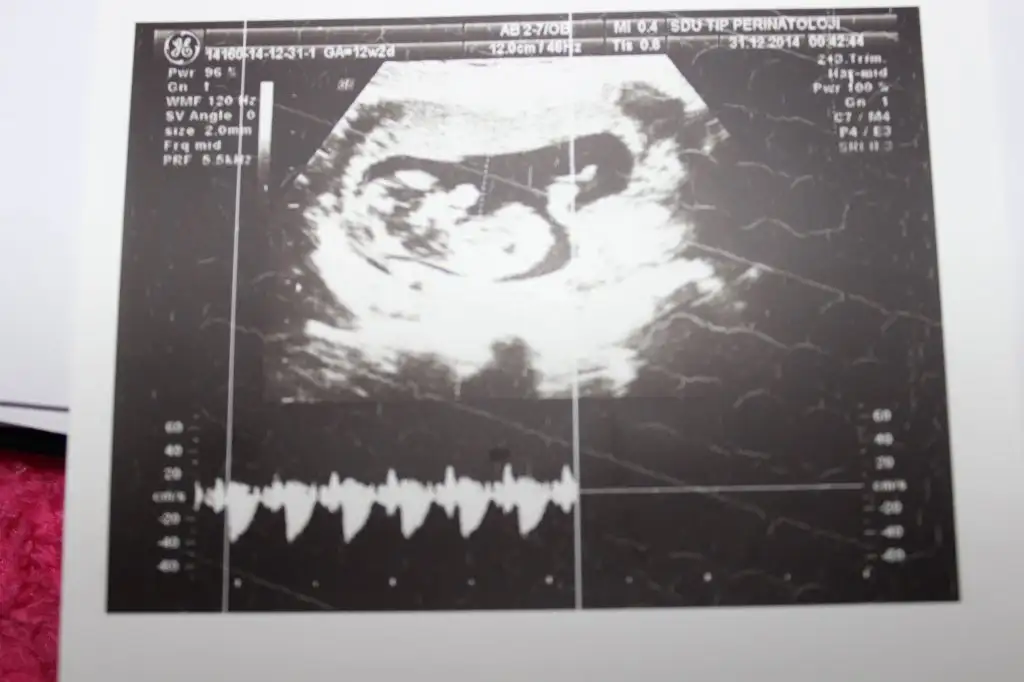

dr soylemeden siz gorun genital nub teorisi ( bebegin cinsiyeti)

IMG_1301.webp IMG_1302.webp IMG_1303.webp IMG_1306.webp

Kiz dedigim foto on haftalikmis zaten canm o haftada hepsi kiz gibi gorunur bilseydim kucuk derdim son fotodan belli erkek bebegin geliyor bence

arkadaşlar bana kız diyende var erkek diyende benim bebeğim belli etmiyomu yaa bnde anlayaadım ne paralel ne yukarı dogru :D